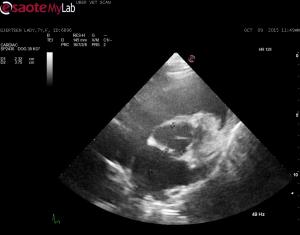

– echo showed normal LV parameters (no eccentic hypertrophy documented) however EPSS is elevated and FS% decreased

– subjectively, I don’t think the heart looks like it is contracting well

Innapropriate wall thickening

Innapropriate wall thickening with dilated L ventricular chamber elevated EPSS and poor FS to me indicates cardiomyopathy. Consider a mitral inflow study to get some sort of idea of L atrial pressure. I am suprised the L atrium is not more dilated.